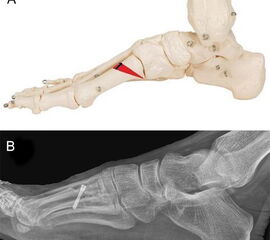

Um die Steilstellung des ersten Os metatarsale und die damit verbundene Entwicklung eines plantaren Ulkus unter MTK-1 zu verhindern, kann in minimalinvasiver Technik durch eine schräg verlaufende, dorsalbasige Keilosteotomie im proximalen Anteil des Os metatarsale I das Metatarsaleköpfchen angehoben werden. Diese Maßnahme führt zu einer Druckreduktion und in der Regel zu einer Abheilung des Ulkus. Die Osteotomie wurde 1998 erstmalig in der offenen Technik beschrieben, wird aber inzwischen auch in minimalinvasiver Technik durchgeführt 25. Über einen dorsomedialen Hautschnitt wird am ersten Strahl ein dorsalbasiger, nach distal geöffneter Keil reseziert (Abb. 11). Der Eintrittspunkt der Fräse befindet sich knapp distal des Tarsometatarsale-I-Gelenks. Die plantare Kortikalis des Os metatarsale I wird dabei erhalten. Die Breite des dorsalen Keils bestimmt das Ausmaß der Korrektur und kann durch Verwendung einer entsprechenden Fräse modifiziert werden. Durch einen Keil mit einer Basis von 3,4 mm lässt sich das Os metatarsale I um ca. 5° anheben. Hat der dorsale Keil eine Basis von 6,7 mm, wird die Achse des Os metatarsale I um 10° nach dorsal korrigiert (Abb. 12). Wird eine Korrektur von ca. 5° angestrebt, bietet sich an, eine Fräse mit einem Durchmesser von 2 mm zu verwenden. Der Substanzverlust bei einem Schnitt liegt bei 2-2,5 mm. Für eine weitere Knochenresektion wird die Osteotomie durch plantaren Druck auf das Os metatarsale I Köpfchen geschlossen und die Fräse nochmals durch die geschlossene Osteotomie geführt. Durch mehrmalige Wiederholung dieser Prozedur lässt sich die Korrektur sehr genau einstellen. Für eine Korrektur von 10° oder mehr kann eine Keilfräse mit entsprechend größerem Durchmesser verwendet werden. Nach Schließen der Osteotomie erfolgt die temporäre Fixation mittels eines K-Drahtes und die Osteosynthese mit einer oder zwei Zugschrauben. Die Nachbehandlung beinhaltet eine sechswöchige Ruhigstellung im Verbandsschuh unter Fersenbelastung.

Zum Lesen der Bildbeschreibung und zur Vollansicht bitte das Bild anklicken.

Abbildung 11

Abbildung 12